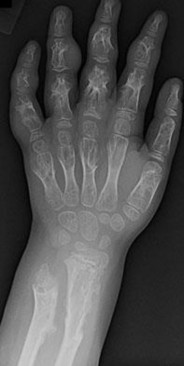

A 45-year-old manual laborer complains of chronic radial-sided wrist pain. He recalls a severe 'sprain' 10 years ago. Radiographs demonstrate scapholunate dissociation with advanced radioscaphoid arthritis. MRI confirms the radiolunate joint is spared, but the proximal capitate shows severe, full-thickness chondral wear.

Which of the following procedures is most appropriate to provide durable pain relief while preserving motion?

Explanation

The patient has Scapholunate Advanced Collapse (SLAC) pattern of the wrist. Stage III SLAC involves the capitolunate joint, while the radiolunate joint characteristically remains spared. Because the capitate head is severely arthritic, Proximal Row Carpectomy (PRC) is contraindicated, as it relies on a healthy cartilage interface between the capitate and the lunate fossa. Scaphoid excision with four-corner fusion (capitate, hamate, lunate, triquetrum) is the procedure of choice.